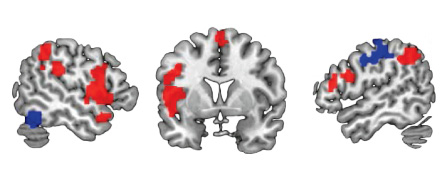

Depending on which part of the brain gets nudged, tDCS can influence things like attention, working memory, visual abilities and mathematical skills. For instance, stimulation to the top of the brain caused 15 healthy people to learn a made-up number system better than healthy people who received no stimulation, and the benefit lasted months after the stimulation stopped, neuroscientist Roi Cohen Kadosh of the University of Oxford and colleagues reported in Current Biology in 2010.

tDCS may also alleviate symptoms of depression, other small studies suggest. In a randomized trial of 120 people with moderate to severe depression, tDCS, with positive stimulation (anode) over the left side of the brain and negative (cathode) over the right, boosted the effects of the drug sertraline, or Zoloft, scientists reported in 2013 in JAMA Psychiatry. Over a six-week period, people who received both tDCS and sertraline scored on average 11.5 points better on a depression rating scale than people who received placebos. (A drop of three points was considered clinically relevant.) tDCS alone caused a smaller drop — 5.6 points — versus sham, and sertraline alone caused an even smaller drop: 2.9 points less than placebo.